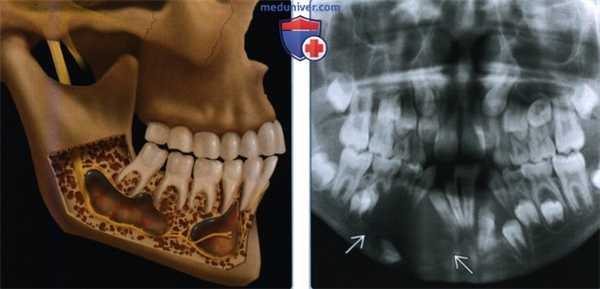

(Слева) На рисунке нижней челюсти (вид сбоку, кортикальный слой удален) показаны множественные кератокистозные одонтогенные опухоли, типичные для синдрома базальноклеточного невуса. Опухоли раздвигают корни зубов и смещают нервы.

(Справа) На ортопантограмме визуализируется крупное рентгенпрозрачное образование с экпансивным ростом в нижней челюсти слева, парамедианно, с выраженным смещением вовлеченных зубов.3. КТ при синдроме базального клеточного невуса: